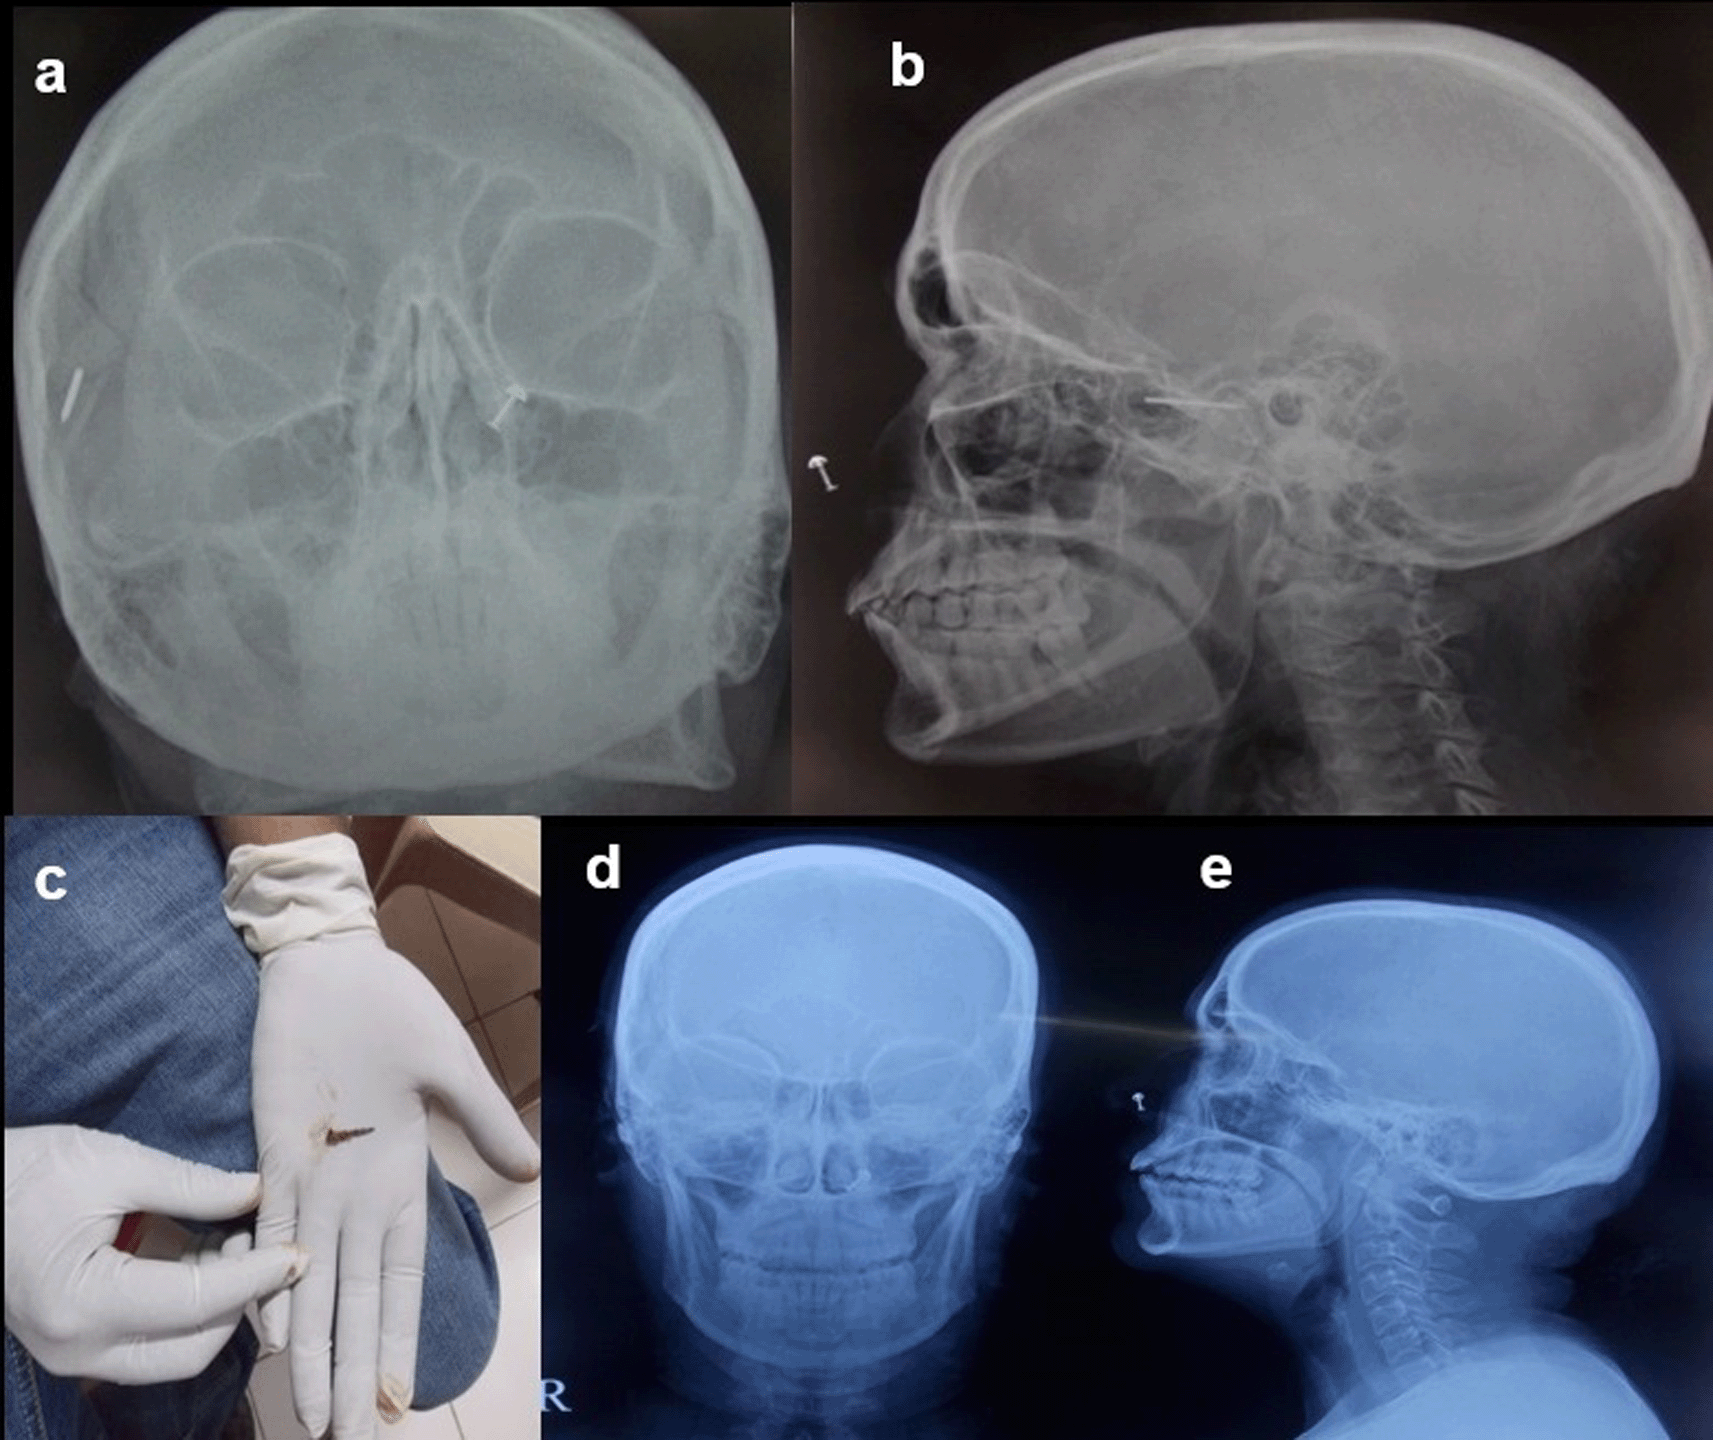

Case 8: A 50-year-old woman came for cervical spine. The patient was taken for an MRI scan when she complained of a severe headache. Radiograph skull AP & Lateral view was done, which showed a radiodense nail-like structure in scalp on right side. On asking, the patient gave a history of trauma ten years back and did not know that she had a nail in her scalp. It was removed under local anaesthesia.

Some metallic foreign bodies can be accidentally diagnosed during an MRI or CT study due to artefacts or sometimes due to pain as they enter the magnetic field12 (Figure 8a,b).

The nail removed under ultrasound guidance (c). Normal radiograph skull A-P & Lateral view post removal of the foreign body (d,e).